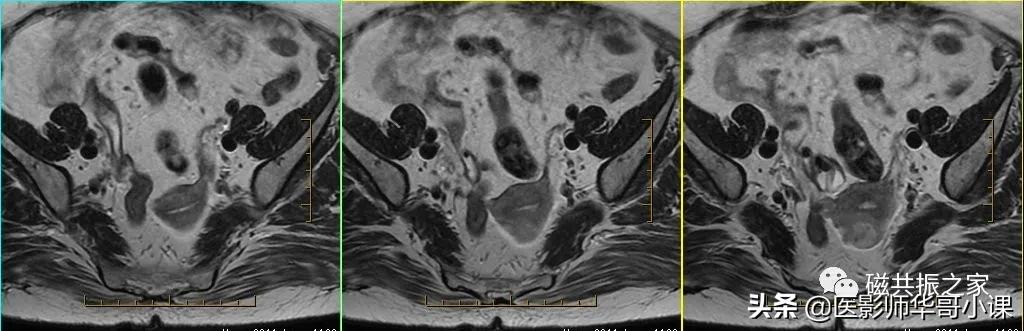

子宫MRI扫描前应先行1-2个大范围的 全盆腔 扫描序列,通常为大范围的T1WI和T2WI 压脂序列;在冠状位和矢状位上定位,按照常规的横轴位扫描即可。

行大范围扫描的目的:

1.了解盆腔内病变的大体情况。

2.观察盆腔内出血、转移、周围侵犯等情况。